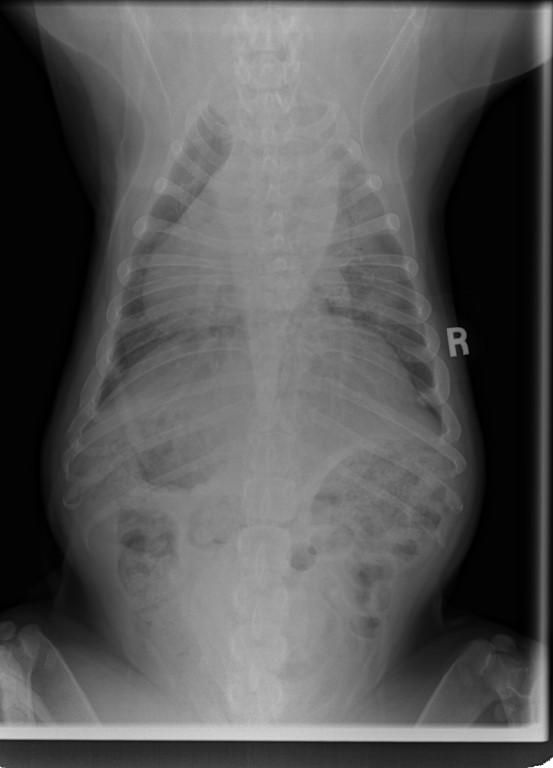

I took him to KAH as I wanted to get an updated weight on him for he had dropped down to 19 kgs and, he was back up to 20 kgs, so giving him the extra 1.5 cups daily as his body fought these infections etc., has helped. He was 20.2 kgs the day he went to his temp foster home.

I cannot stress enough about how I want to see him between 19.8 kgs and 20.5 kgs. He is not to become obese and, of course, we do not want him skinny. Lean and healthy! He is so fit and, looking like a Bulldog should, not what people' 'think' bulldogs should look like – rotund with stomachs protuding.

Even per his Vet at KAH, that he is on Baytril and, that he is battling these infections, is a bit concerning.